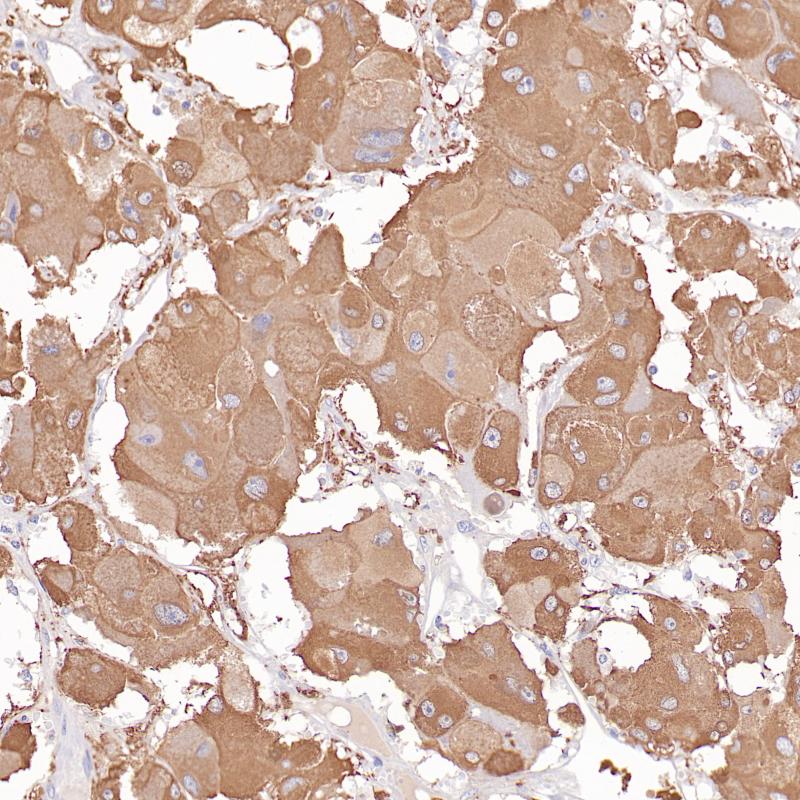

Bcl-2是分子量为25kDa的线粒体内膜蛋白,是一种细胞凋亡的抑制因子,参与细胞凋亡的调控。Bcl-2正常表达于套区和边缘区的小B细胞和部分T细胞、胸腺髓质细胞和正常乳腺上皮细胞。在多数软组织肿瘤中阳性表达,如孤立性纤维瘤、滑膜肉瘤等。该抗体也用于滤泡性淋巴瘤与反应性滤泡增生的诊断及鉴别诊断。

扁桃体、滤泡性淋巴瘤